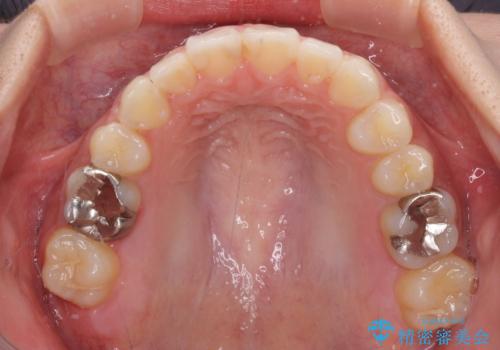

- 上下の八重歯を気にして来院された患者様です。

上下ともに八重歯の後ろの歯を1歯ずつ抜歯し、補助装置(リンガルアーチ)を用いて八重歯の位置を改善し、その後インビザラインにより矯正治療を行うこととしました。